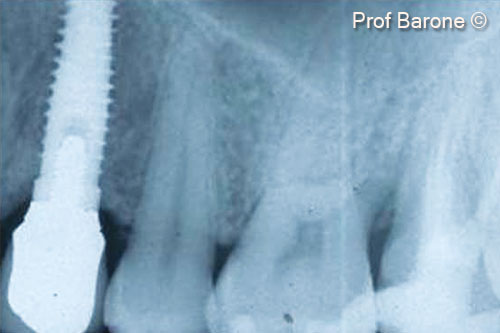

Một bệnh nhân nữ (27 tuổi) có biểu hiện nhiễm trùng cấp tính và mủ từ lỗ rò ở miệng.